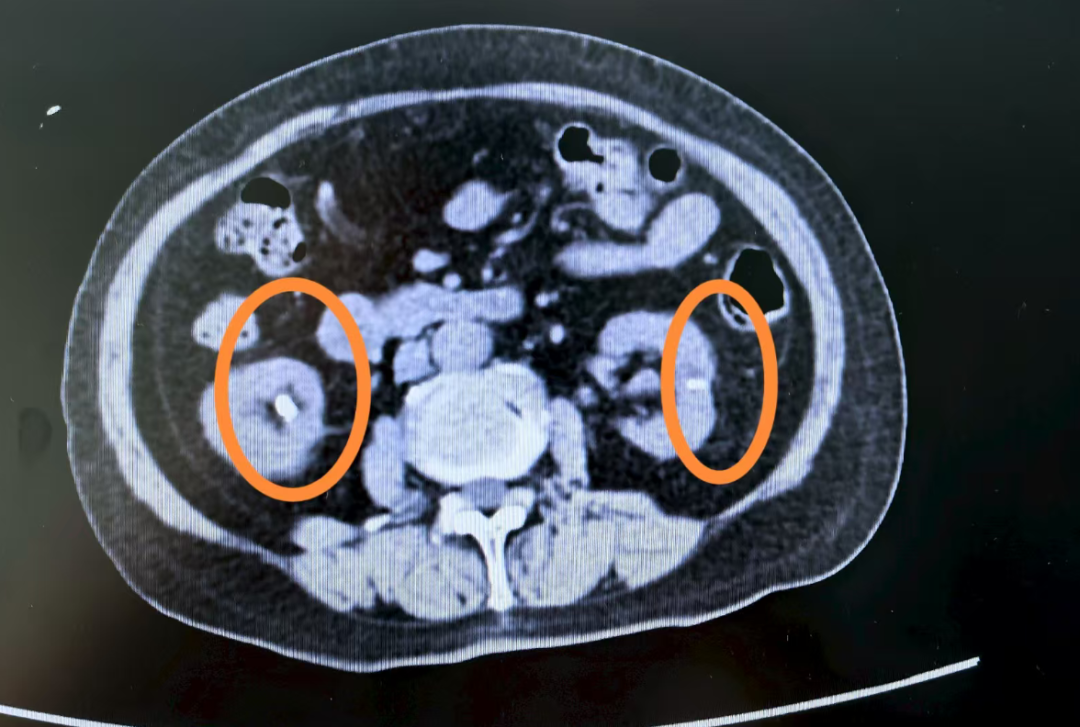

几年前,一位 85 岁的老奶奶同样被确诊为「异位甲旁亢」,但由于高龄以及家属对手术风险的顾虑,最终选择了保守治疗。可在之后的数年里,她反复发生全身多处骨折,骨盆影像上密密麻麻全是陈旧骨折痕迹,肾脏也长满结石,最后只能依靠轮椅生活,生活质量极差。

「看到片子上的影像,每个医生都会感到惋惜。」张瑜庆的声音低沉下来,「一旦发生严重的骨质疏松和骨折,很多损害是不可逆的。我们不想再看到第二个这样的病例。」